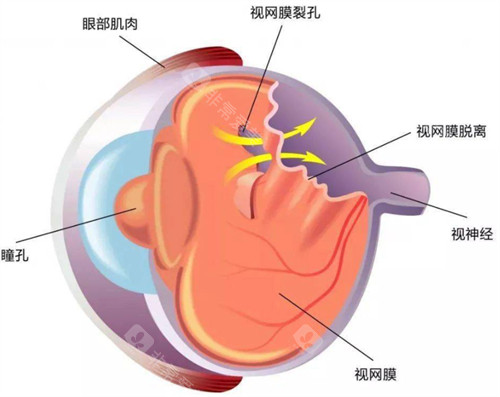

视网膜脱落的治疗方法有多种。对于尚未发生脱离的视网膜裂孔,可采用激光治疗,利用激光封闭裂孔,防止视网膜脱落。传统的巩膜环扎术和巩膜外加压术,适用于单纯的早期视网膜脱离。

而对于病情复杂的视网膜脱落,如伴有玻璃体混浊、牵拉等情况,玻璃体切割视网膜复位联合手术是常用的治疗方式。

这种手术对技术要求高,需要特殊的设备及术后护理。此外,渗出性视网膜脱离主要以治疗原发病为主。